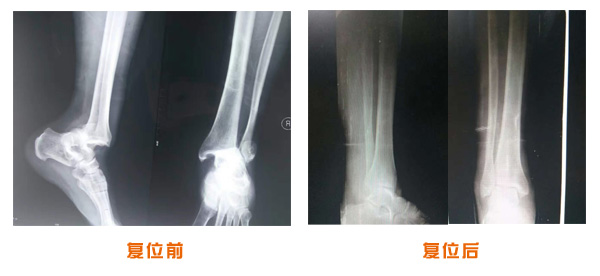

復(fù)位前后對比